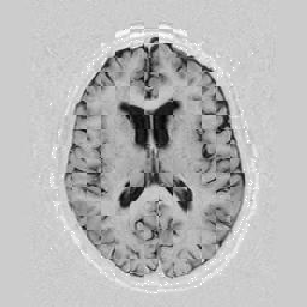

Another larger group of experiments enabled me to study the effects of multi-scale NRR. The results are shown in the form of chequerboard images in Figure [*]. In terms of resolution levels, higher numbers mean that the images are coarser.

Figure: Multi-scale NRR (increasing resolution). From left to right, top then bottom:before NRR; after 5 iterations of NRR at level 2 (higher is coarser); after another 5 iterations of NRR at level 1.